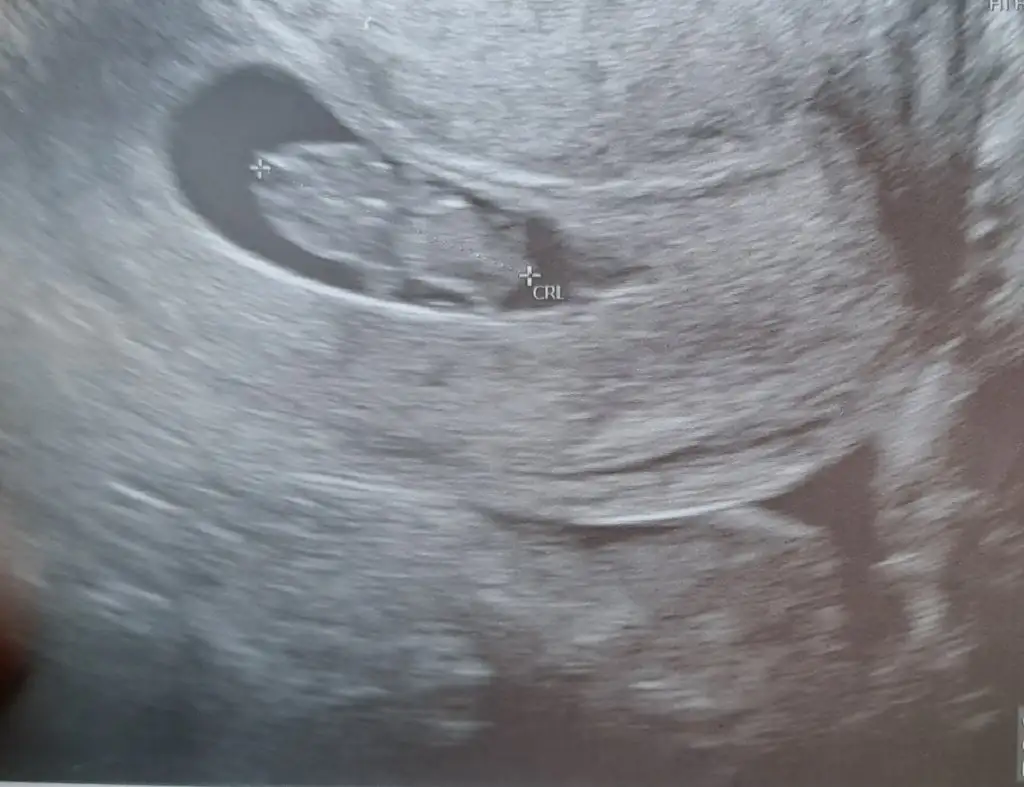

5 ve 14. haftaya kadar olan ultrason fotolarınızı paylaşın. Vajinadan mı yoksa karından mı çekildiğini ve kaç haftalık olduğunu da mutlaka belirtin.:anneadayı: